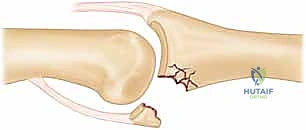

* FIG 2 • A. Avulsion fracture. Avulsion fractures usually are caused by a forced PIP joint hyperextension. The fragment is not comminuted and involves less than 30% of the joint surface. The PIP joint is most often stable.

* FIG 2 • B. Impaction shear fracture. This type of PIP fracture-dislocation is caused by a longitudinal load to the joint. The fracture fragments are comminuted and impacted into the middle phalanx. The joint reduction often is unstable.